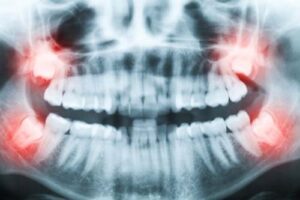

Visdomständer kan orsaka smärta, infektioner eller trångställning när de bryter fram. Vid problem rekommenderas borttagning.

Vi gör alltid en röntgenundersökning för att planera ingreppet och ser till att du får en trygg och smidig behandling.